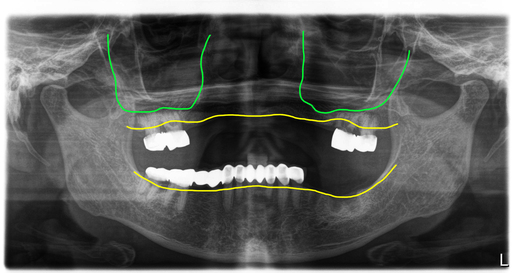

초진시 파노라마 엑스레이입니다. 처음 방문하셨을 때에는 상악에 부분틀니가 불편해서 해결하려고 오셨는데 임플란트 2개 정도 심어서 하는 임플란트 틀니 치료를 원하셨어요.

그래서 당시 환자는 이미 빠진 치아 외에 몇개의 치아에 이차우식과 치주염이 진행되어 빠진부위 임플란트와 문제가 있는 치아만 먼저 치료를 하기로 계획을 세웠습니다.

위에 남아있던 치아들 중 3개는 괜찮았었는데 이제는 4개 모두 발치를 해야 하는 상태였고, 아래도 브릿지 속 치아들이 모두 썩어서 브릿지가 흔들리고 있었어요.

그래서 결국 3년 전의 치료계획대로 치료를 할 수 없는 상태여서 전체 치아를 모두 제거하고 전체임플란트를 하기로 결정했습니다.